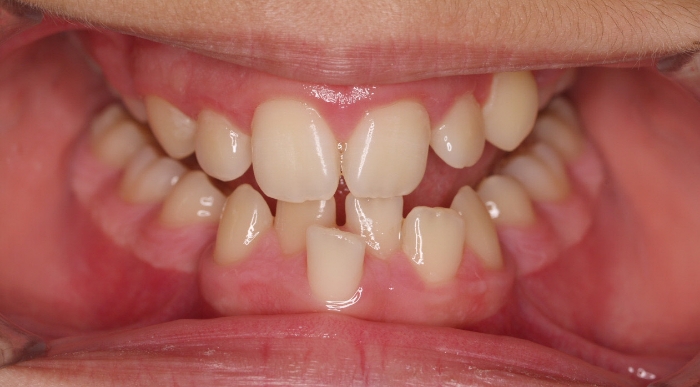

El paciente M.C. acude a nuestra consulta por:

– Apiñamiento importante

– Perfil convexo

– Forma arcada estrecha

-sobremordida

Con lo que decide realizarse un tratamiento de ortodoncia de duración de 26 meses con brackets smartclip 022 de acero.

Fotos antes tratamiento: